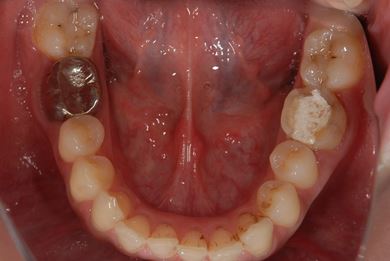

| 性別/年齢 | 女性 / 30歳 | ||||||||||||||||||||||||||||||||

| 主訴 | 銀歯がはずれた奥歯にひびが入っており、抜歯しなければいけないため、インプラントの治療相談を希望。 | ||||||||||||||||||||||||||||||||

| 治療内容 | インプラント1本、メタルボンドセラミック1本 | ||||||||||||||||||||||||||||||||

| 総治療費 | 401,363円 | ||||||||||||||||||||||||||||||||

| 治療期間 | 5ヶ月 |